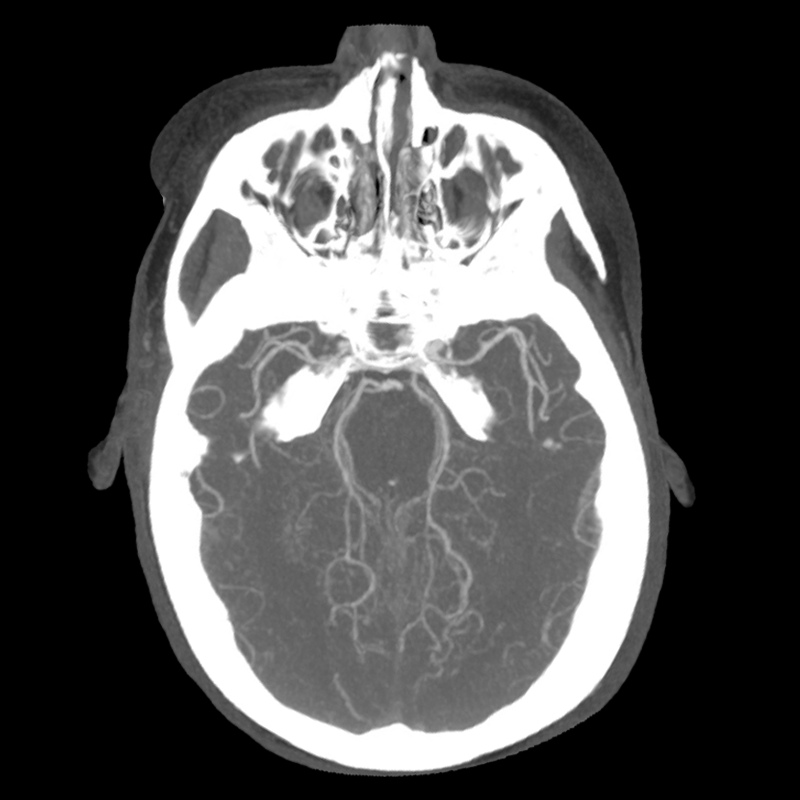

You arrive at the patient's room. You quickly examine her. Her left pupil is truly dilated and unreactive. Her right pupil is also dilated and unreactive, and also deviates to the right. She is unable to follow commands but is moving her extremities spontaneously. The right side of her body seems to be moving slightly less than her left. You escort the patient with RRT and your neurology colleague to radiology, where a non-contrast head CT and CTA head/neck are obtained.

The non-contrast head CT looks generally similar to her prior scan. There's no new hemorrhage anywhere. There's no mass effect causing midbrain compression. The vessel imaging also looks unrevealing-- a slightly hypoplastic right A1 segment, but no clear LVO in either the anterior or posterior circulation. There's no vasoconstriction.